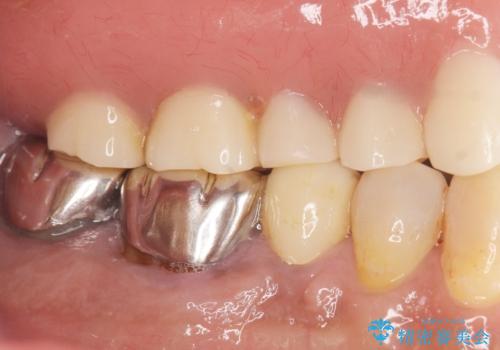

予算を抑えて審美的に咬合を回復することができ、ご満足頂けました。

マグネット(磁石)により入れ歯がはずれにくく動揺しにくいため、入れ歯安定剤などを使うことなく食事やお話も問題なくできると喜んで下さいました。

入れ歯の種類:金属床義歯 マグネットデンチャー